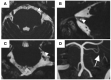

Oral cenesthopathy (OC) is characterized by unusual oral discomfort without corresponding evidence, and it has often been categorized as "delusional disorder, somatic type". Regarding possible causative factors of OC, involvement of neurovascular contact (NVC) of the trigeminal nerve, which transmits not only pain but also thermal, tactile, and pressure sensations, has never been observed yet. This study aimed to investigate the relationship between clinical characteristics of unilateral OC and the presence of trigeminal nerve NVC. This is a retrospective comparative study that involved 48 patients having predominantly unilateral OC who visited the Psychosomatic Dentistry Clinic of Tokyo Medical and Dental University between April 2016 and February 2019. Magnetic resonance imaging was performed to assess NVC presence. The Oral Dysesthesia Rating Scale (Oral DRS) was used to assess the various oral sensations and functional impairments besides psychometric questionnaires. Clinical characteristics were retrospectively obtained from the patients' medical charts. NVC was present in 45.8% (22/48) of the patients. There was no significant difference in sex, age, psychiatric history, oral psychosomatic comorbidity, and psychometric questionnaire scores between patients with and without NVC. However, compared to the patients with NVC, the patients without NVC had significantly higher scores for overall subjective severity of OC symptoms (p = 0.008). Moreover, patients having predominantly unilateral OC without NVC showed significantly higher scores in symptom severity and functional impairment of the following parameters: movement (p = 0.030), work (p = 0.004), and social activities (p = 0.010). In addition, compared with the patients with NVC, the patients without NVC showed significantly higher averages of the total symptom severity scale (SSS) and functional impairment scale (FIS) scores in the Oral DRS (p = 0.015 and p = 0.031, respectively). Furthermore, compared with the patients with NVC, the patients without NVC had significantly higher numbers of corresponding symptoms in both the SSS and FIS (p = 0.041 and p = 0.007, respectively). While NVC may be involved in the indescribable subtle OC symptoms, more complex mechanisms may also exist in OC patients without NVC, which yield varying and more unbearable oral symptoms.